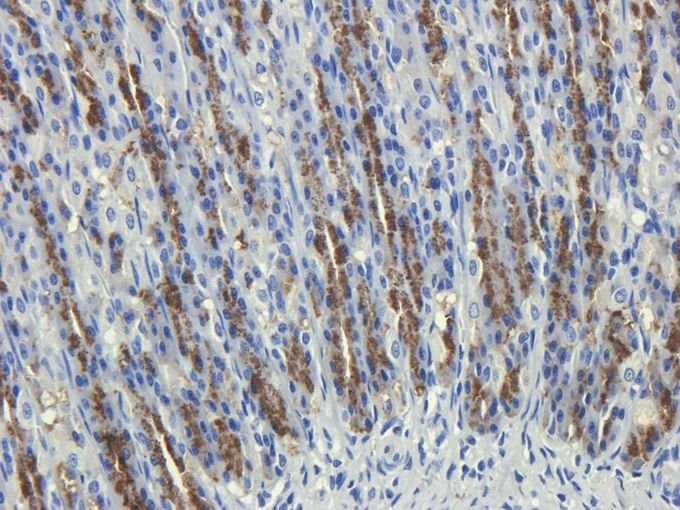

IHC-P analysis of rat stomach tissue using GTX37450 CD35 antibody.

Dilution : 2.5μg/ml